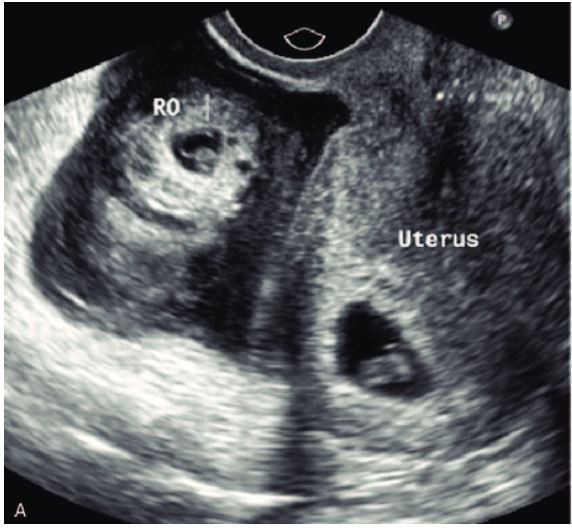

The incidence of heterotopic pregnancy with extrauterine gestation situated in the cornual location is not known, nonetheless, the incidence of cornual heterotopic maternity is approximated to be 1/3600 IVF pregnancies. We present one situation of spontaneous cornual heterotopic pregnancy diagnosed by ultrasound and also handled by laparoscopic-guided methotrexate shot into the cornual sac.

The diagnosis of CHEP can be challenging due to its rarity and the lack of specific symptoms. However, early diagnosis is critical for reducing the risk of rupture and hemorrhage. Common presenting symptoms of CHEP include abdominal pain, vaginal bleeding, and positive pregnancy test. Ultrasound imaging is the primary diagnostic tool for CHEP, although it may not always be able to differentiate between a cornual ectopic pregnancy and an interstitial ectopic pregnancy. Magnetic resonance imaging (MRI) can also be used to confirm the diagnosis and provide more detailed information about the location and size of the pregnancy.